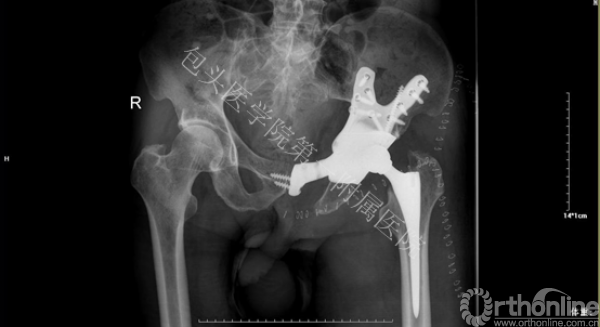

2015年3月13日包头医学院第一附属医院骨科顺利完成钛合金3D打印骨盆肿瘤假体植入术。

骨盆肿瘤切除后骨缺损的精细化解剖重建一直是世界性难题。传统的标准化假体仍存在诸多问题,如:无法满足不同缺损类型的重建要求,力学不稳定导致术后断裂,术后功能修复差距也很大。为此,董乐乐教授团队与西安交通大学机械制造系统工程国家重点实验室生物制造研究团队共同协作,经反复论证和数字化设计,经过3D打印为患者量身定制了个性化假体。

术前根据患者的CT数据,设计出解剖结构和肿瘤切除后与骨缺损部位完全匹配的假体,再应用“激光3D打印成形”制造出符合患者生理解剖和生物力学要求的钛合金金属假体。手术完整切除骨盆肿瘤,精确安放定制假体,达到良好的解剖和功能重建。最终,为患者提供精确化医疗和个性化医疗的服务。